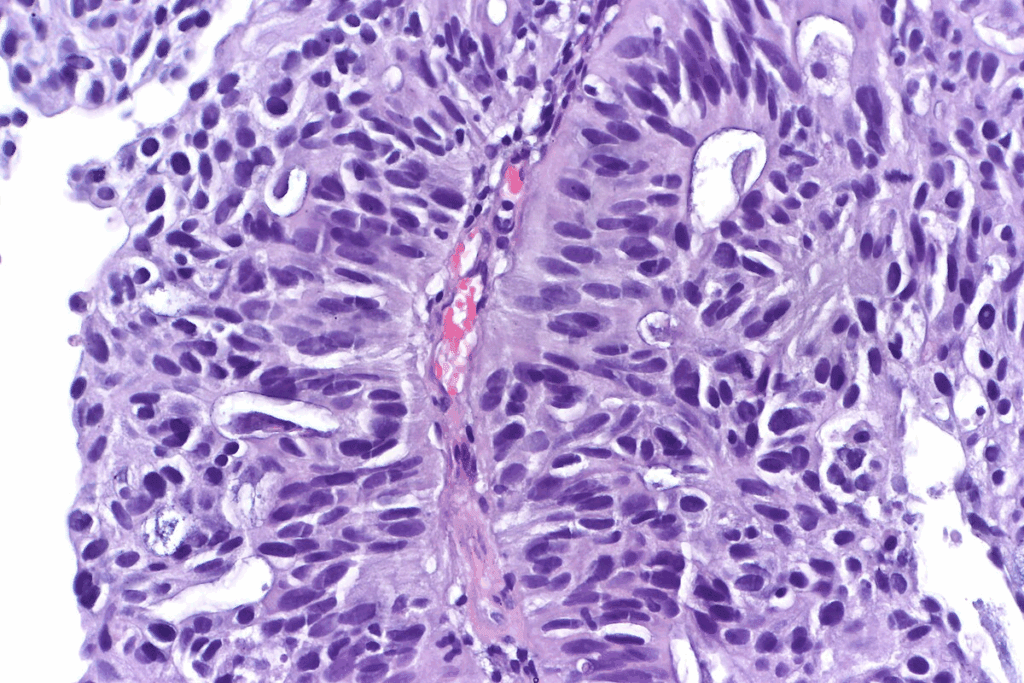

Leukoplakia and Erythroplakia

Leukoplakia shows up as white or gray patches in the mouth. It’s a common sign linked to smokeless tobacco. “Leukoplakia is often seen as a warning sign for oral cancer,” and can turn into cancer if not treated.

Erythroplakia, with its red patches, is rarer but more likely to become cancerous.

Both conditions need close watching and sometimes a biopsy to check their severity. People using smokeless tobacco should watch for any unusual mouth patches or lesions. If they see something odd, they should get medical help right away.